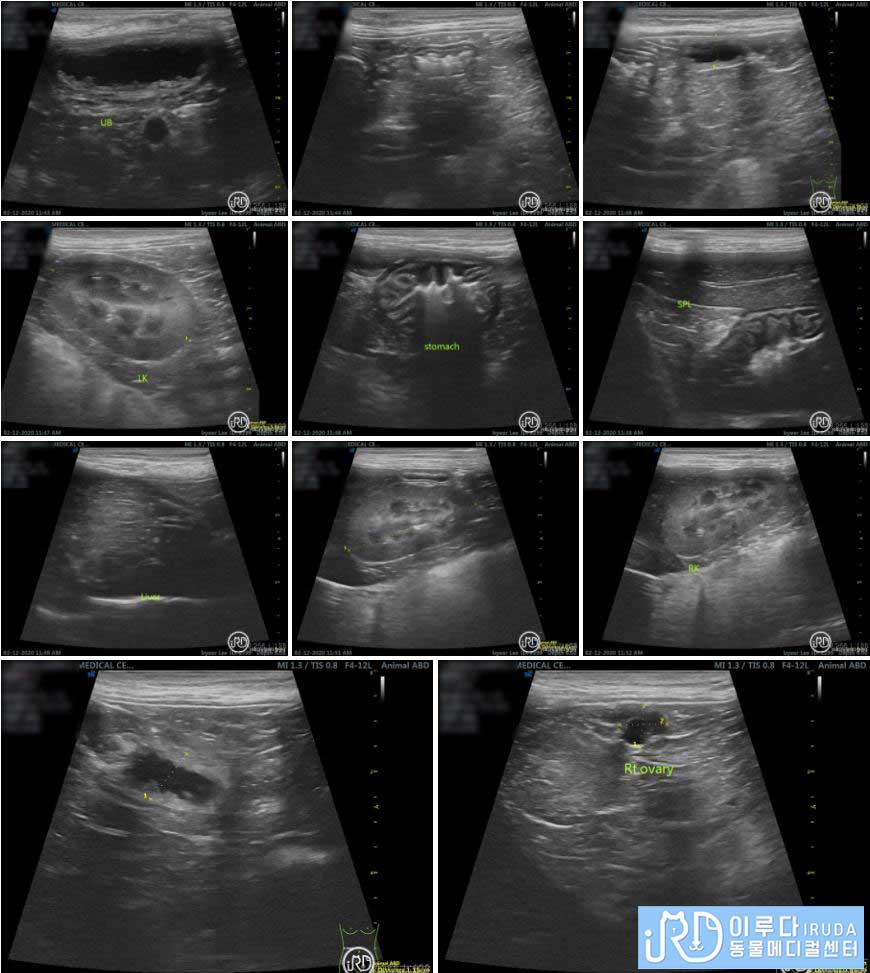

복부 초음파 검사

복부 초음파를 통해 살펴본 결과, 장 내에 있는 다수의 가스가 확인되었습니다. 또한 간, 신장, 방광 등의 장기에는 문제가 없었지만 자궁의 크기가 비대하다는 것을 확인할 수 있었습니다. 방사선 검사와 복부 초음파를 통해 확인한 결과, ㅂㅇ는 자궁 수종과 장염으로 진단되었습니다.